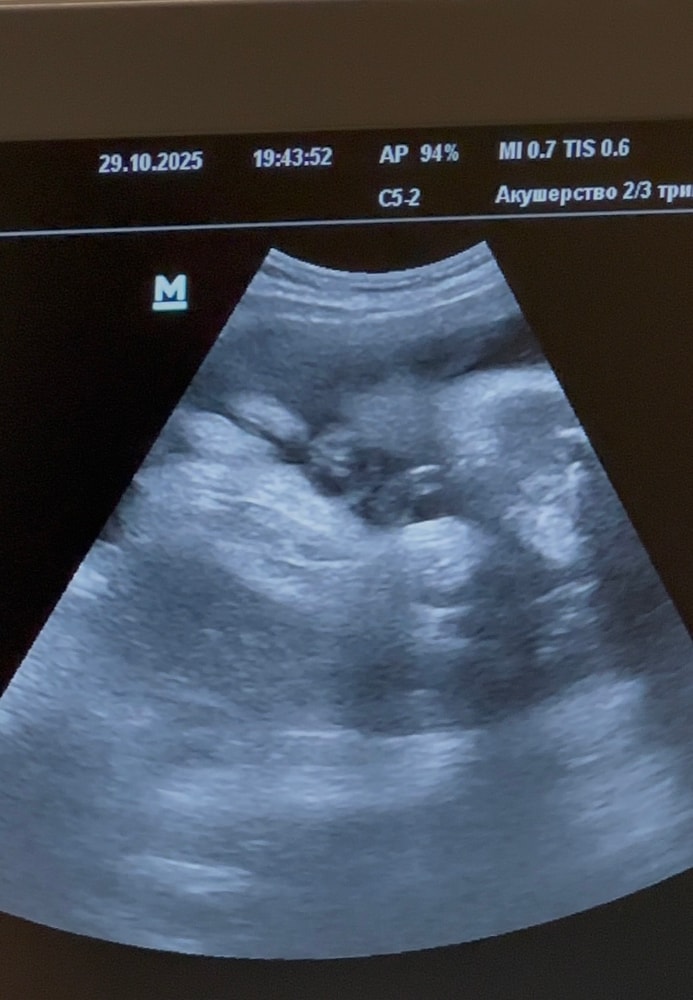

Девчонки, пропала что-то я, давно не заходила. А все потому что очень переболели с мужем. Врачи говорят была какая то корона только кишечная. Переболели 3 недели и вот по тихоньку идем на поправку. Но суть не в этом, сегодня были на узи, а точнее, на втором скрининге